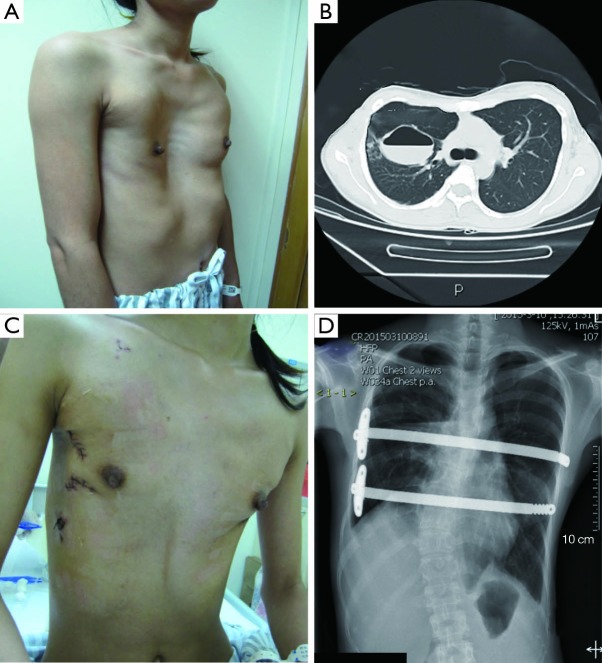

Figure 3.

(A) Appearance of an extremely severe pectus excavatum patient before surgery; (B) chest CT image of a pectus excavatum patient before surgery; (C) appearance of a pectus excavatum patient after Nuss procedure; (D) chest X-ray of a pectus excavatum patient after repair; (E) appearance of a pectus excavatum before bar removal; (F) chest CT of a pectus excavatum patient after bar removal.